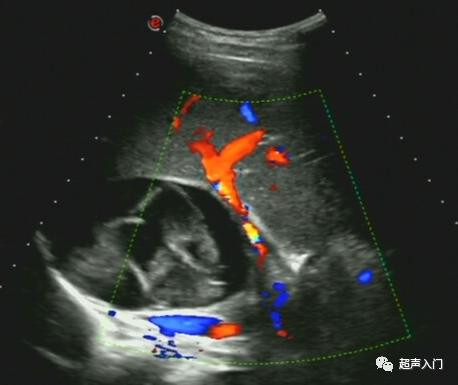

彩色多普勒:表现为无彩色血流信号,但在病灶并发感染则可在炎性区出现彩色血流。

超声造影:病灶未见增强,呈无回声团块,境界清楚。